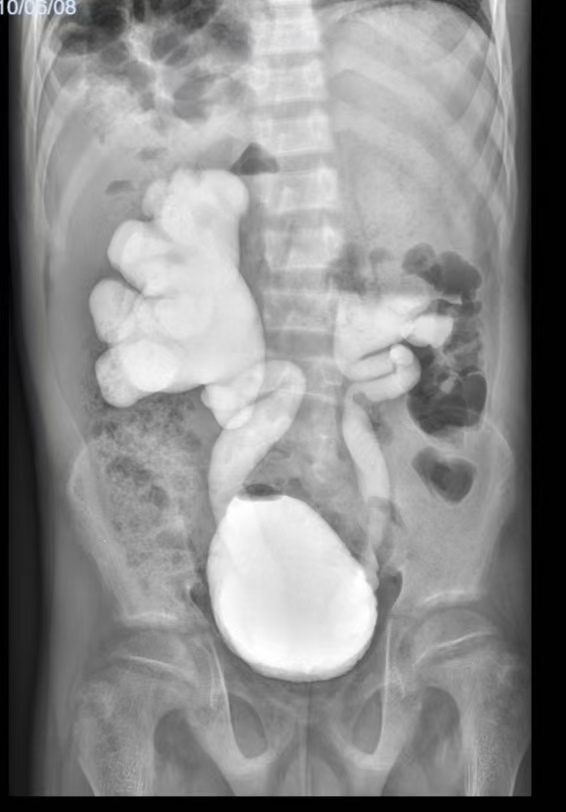

(患者膀胱造影早期)

2025年7月底,该患者转诊至我院泌尿外科。文永安主任高度重视,立即组织科室诊疗团队对患者6年的复杂病史进行全面梳理,并制定了针对性的检查方案。通过膀胱造影检查,精准评估患者上尿路动力情况及膀胱收缩功能;同时,指导护理团队同步记录患者排尿日记,全面、细致掌握患者病情细节。凭借丰富的临床经验及严谨的病例分析判断,泌尿外科团队突破了此前的诊断局限,最终明确诊断为 “膀胱输尿管反流、肾盂积水、肾功能不全、代谢性骨病、尿道下裂、先天性膝外翻”,为后续精准治疗方案的制定奠定了关键基础。